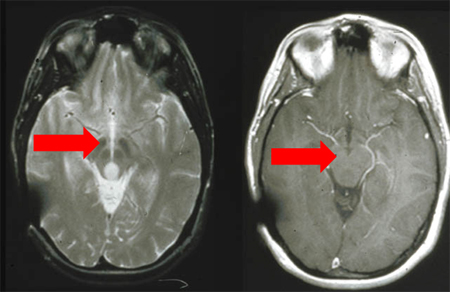

Deverão ser solicitadas uma ressonância nuclear magnética (RNM) ou tomografia computadorizada (TC) cranioencefálicas, se houver suspeita de uma causa orgânica do SNC.[6] As indicações para uma RNM ou TC abrangem:

Uma história de trauma cranioencefálico (para detectar sangramento ou hematoma intracraniano)

Presença de sinais neurológicos focais

Cefaleia suspeita ou alteração no padrão da cefaleia

Início em idade tardia ou deficit cognitivo pronunciado, sugestivo de demência.

Sintomas psicóticos atípicos, como alucinações visuais

[Figure caption and citation for the preceding image starts]: RNM: T2 e T1 pós-contraste, demonstrando glioma do teto mesencéfalo (grau II).Do acervo pessoal de Karine Michaud, University of California, San Francisco; usada com permissão [Citation ends].